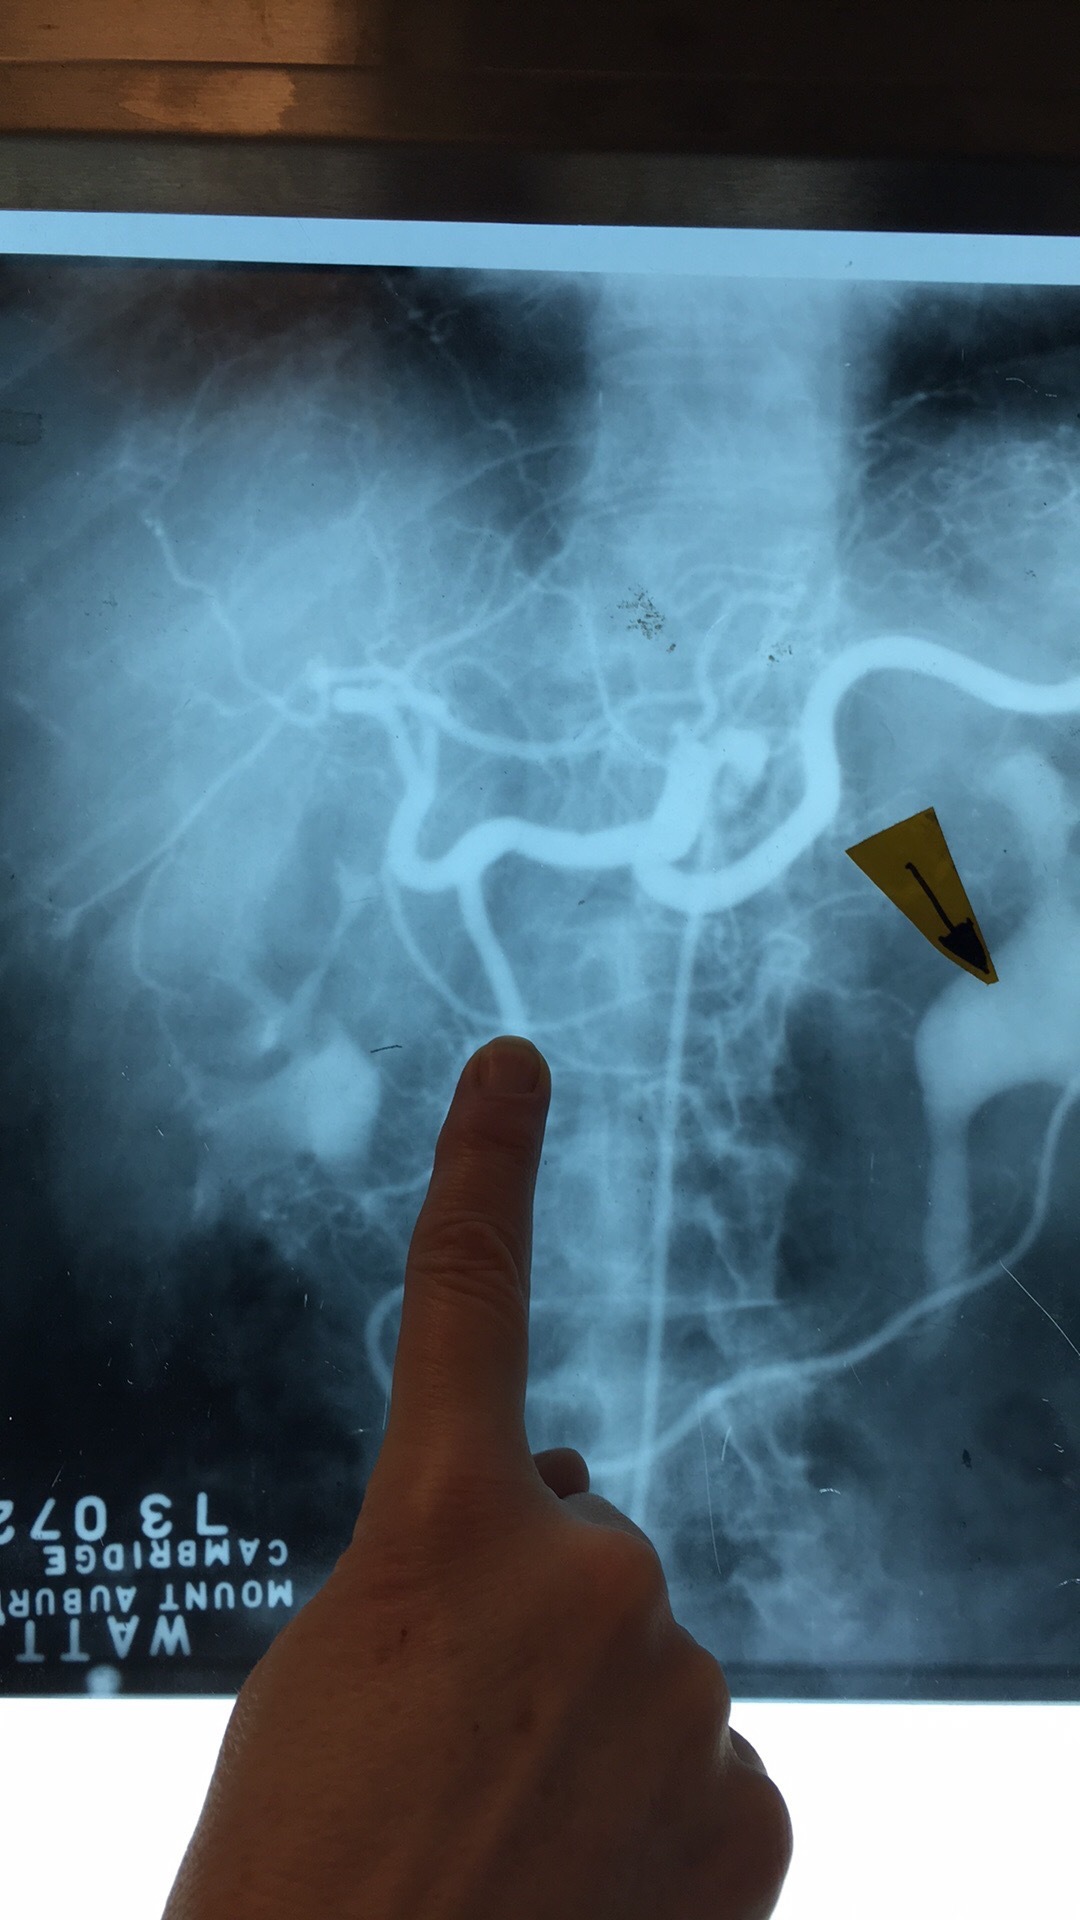

Which artery? What are the branches?

Celiac Trunk. Left Gastric Art, Common Hepatic Prtery, and Splenic Art